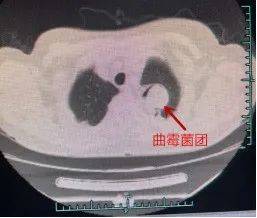

感染曲霉菌 , 整个左肺快要“沦陷”

原来 , 章阿姨得的是肺曲霉病 。 “这个病比较罕见 , 即使在市一医院这种三级综合性医院中 , 一年也很难遇到几个 。 ”冯兴介绍 。

因为曲霉菌的感染和侵蚀 , 章阿姨左肺上叶已经出现了一处鸡蛋大小的空洞 , 而且正在慢慢变大 , 再发展下去可能整个左肺都要“沦陷”!

医师立刻予以抗真菌药治疗 , 使之在肺内形成了稳定的曲菌球团 , 并安排住进病房 , 准备择期手术 。